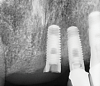

(4.) A failed implant that underwent mechanical overloading leading to fracture of the coronal portion adjacent to the implant-abutment connection.

Figure 4